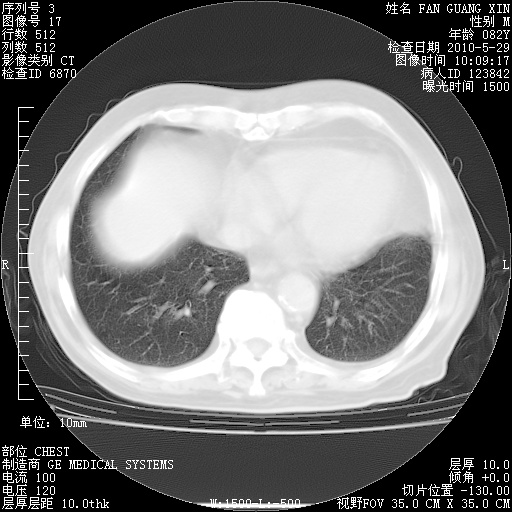

再治疗10天后的肺部CT